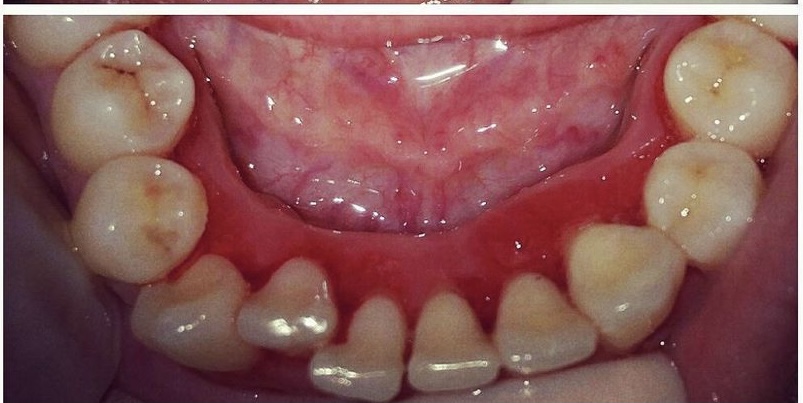

Bleeding contributes to worsening morbidity by the acute toxic state that appears during the 3rd to 5th day of illness following the onset of fever and usually last for 7 days. The most common hemorrhagic manifestation are bleeding nose, skin hemorrhages, scattered petechiae, ecchymoses and gastrointestinal hemorrhages and that included spontaneous bleeding from the gums and a purpuric rash. Most of these cases reported with declining platelet count, a condition knows as for thrombocytopenic purpura with the numbers as low as 2,000. (normal range :150,000 to 400,000).Laboratory tests are positive for immunoglobulin M (IgM) antibodies to the virus. Treatment includes managing fever and dehydration to administration of steroids for up to 10 days and platelet transfusion in the most sever form.

The disorders of blood or blood forming organs can have a profound effect on gums and bones of the jaw. Ecchymosis and petechiae observed most often in the soft palate area is a sign of an underlying bleeding disorder. Abnormal bleeding from the gums or other areas of the oral mucosa that is difficult to control is an important clinical sign suggesting a hematological disorder. The prompt referral of the patient may save the life of patient and thereby also emphasizes that the dentist can be the first person who can actually diagnose and refer these patients for proper management.